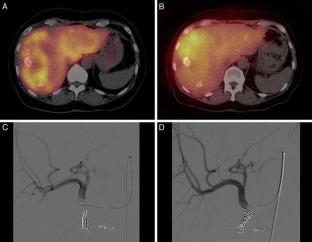

Fig. 4